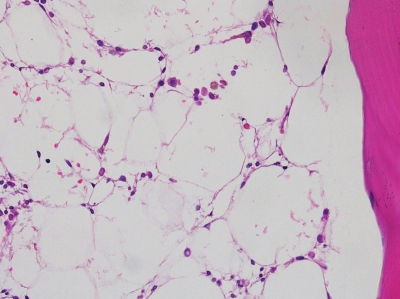

血液所見:赤血球 157万、Hb 5.7 g/dL、Ht 15%、網赤血球 0.3%、白血球 1,800(桿状核好中球 5%、分葉核好中球 13%、好酸球 3%、好塩基球 1%、単球 6%、リンパ球 72%)、血小板 1.3万、PT 99%(基準80~120)、APTT 29秒(基準対照 32.2)、血漿フィブリノゲン 286 mg/dL(基準 200~400)、血清FDP 10 μg/mL以下(基準 10以下)。血液生化学所見:総蛋白 7.0 g/dL、アルブミン 4.2 g/dL、ハプトグロビン 74 mg/dL(基準19~170)、総ビリルビン 0.6 mg/dL、AST 28 U/L、ALT 22 U/L、LD 287 U/L(基準 176~353)、尿素窒素 18 mg/dL、クレアチニン 0.8 mg/dL、尿酸3.6mg/dL、Fe 325 μg/dL。CRP 1.3 mg/dL。骨髄生検のH-E染色標本を別に示す。